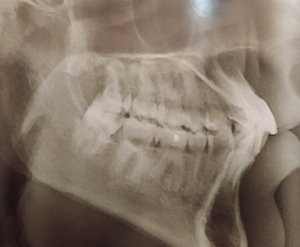

Для установления брекетов врач мне рекомендует удалить верхнюю справа четверку, чтобы поставить на ее место клык, и нижний второй резец справа, аргументируя тем, что так будет быстрее идти лечение, по словам врача корень у этого резца оголен и подвижен (хотя я не чувствую, чтобы он шевелился) и, что все равно в дальнейшем этот зуб я потеряю (и никто, кроме стоматологов не будет замечать, что резцов нижних у меня 3, вместо 4х).

Правда ли то, что этот зуб (резец второй) не здоров? И лучше удалить его, а не 4 нижнюю справа?

По снимку невозможно диагностировать подвижность зуба. Существует методика, при которой возможно удаление и всех восьмых зубов, и, если потребуется, четверок.